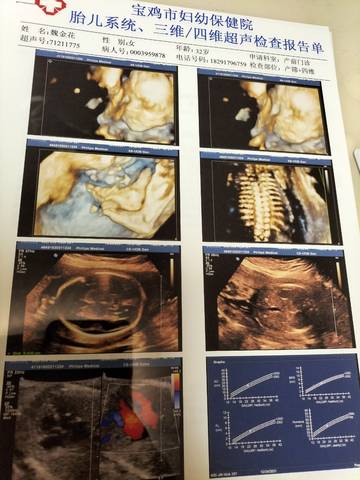

问一下大家四维做出来但说是有染色体,大家看看图片给个建议,

journal_insert_pic_1685693216journal_insert_pic_1685693226

如果有问题的话,应该是要做一下无创或者羊水刺穿吧,这些的话一般都会检查的呢。

建议进一步检查

亲爱的,那你这个还是要去复查一下的呀,有些时候的话不太好说哈,医生可能也判断不了的。